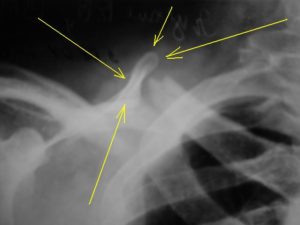

На рентгенограмме обнаруживаются следующие нарушения:

- Клиновидная деформация позвонка,

- Деформация передней поверхности тела позвонка,

- Увеличение межпозвонкового пространства,

- Смещение заднего отдела позвонка в позвоночный канал,

- Подвывих в межпозвоночных суставах.

В первую очередь выполняется рентгенографическое исследование поясничного отдела, причем проводится оно сразу в двух проекциях. Оно дает возможность обнаружить повреждения костной ткани позвонка.